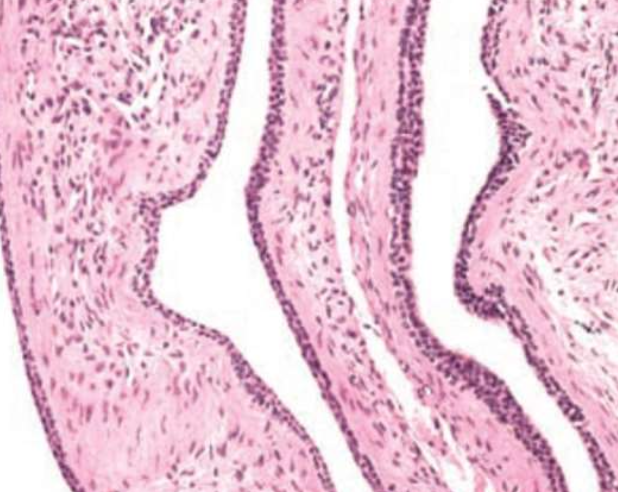

玻片特徵

- Developmental cyst

- epithelial lining 與結締組織交界處平整

- 非發炎型(noninflamed)

- 結締組織鬆散

- 糖胺聚醣基質(glycosaminoglycan ground substance)。

- true cyst

- 兩到四層的扁平非角化上皮

| Glandular Odontogenic Cyst (GOC) | - | 下顎前牙 | 46-51y | 跨中線、無 MAML2 | |

復發、局部侵犯性,吃 cortical bone  |

|||||

| 杯狀細胞, cilia, focal plaques | |||||